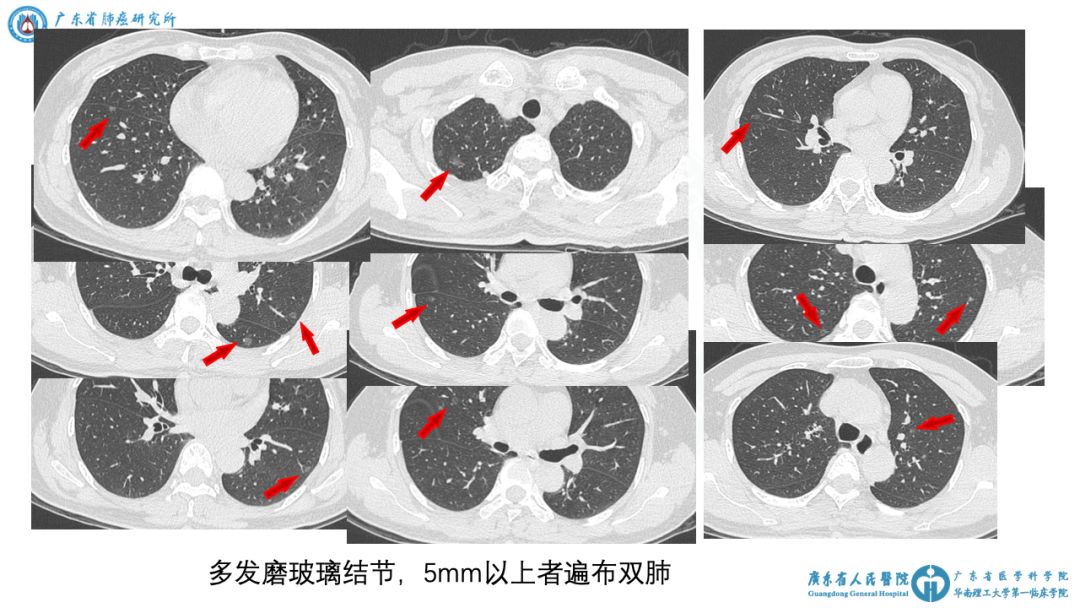

2)2018-10-16 胸CT平扫+增强:①左肺上叶斑片影,考虑慢性炎症。②多发磨玻璃结节,最大者左下肺8mm。③多发磨玻璃结节,5mm以上者遍布双肺。

图表资料